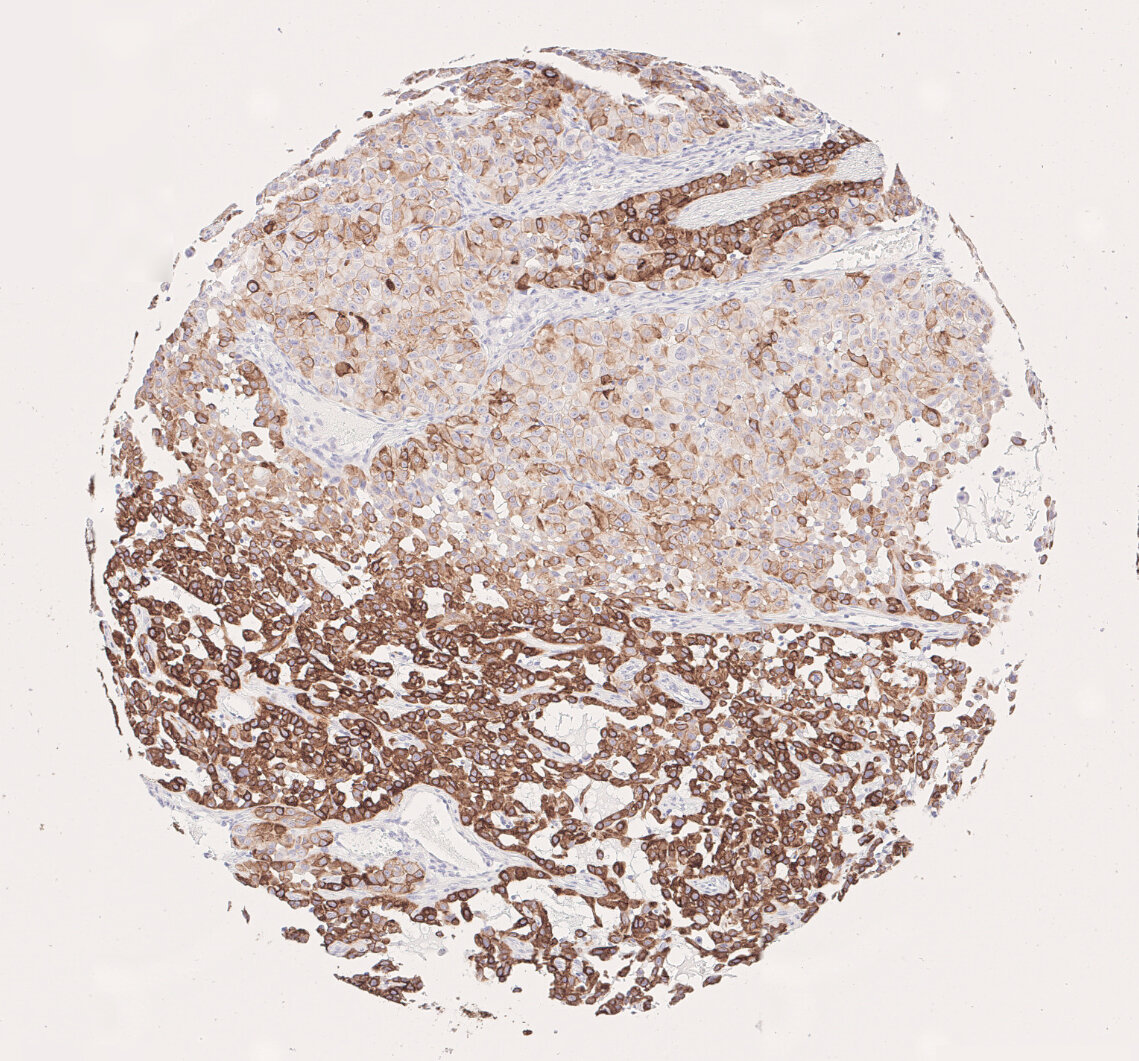

Classification of CK7 status in lung PDX from 0 (negative) to 3+ (very strong expression).

Figure 3: Classification of CK7 status in lung PDX from 0 (negative) to 3+ (very strong expression).

A tissue microarray (TMA) containing 61 annotated patient-derived lung xenograft (PDX) cores was kindly provided by Charles River Laboratories (Freiburg, Germany) and stained using an anti-human Cytokeratin 7 (HS-454 017) antibody on an automated staining platform. Lung cancer xenografts were divided into two types: small cell lung cancer (SCLC; 6/61) and non-small cell lung cancer (NSCLC; 50/61). The latter were further subdivided into NSCLC adenocarcinoma subtype (25/61), NSCLC epidermoid subtype (20/61), and NSCLC large cell subtype (10/61). The CK7 expression level was scored between 0 and 3+ according to staining intensity and percentage of positive cells (Figure 3; Table 1).